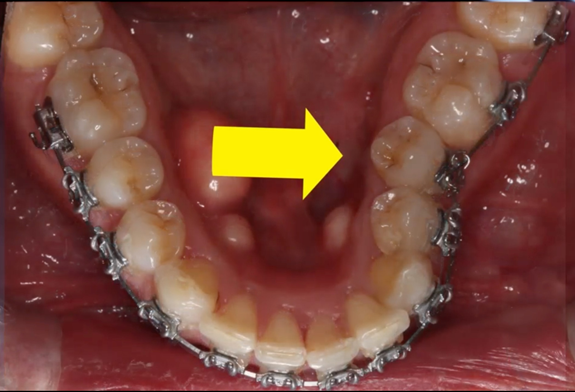

Figure 3A Pretreatment diagnosis of moderate cupping –tooth #20.

Figure 3B Bracketing of tooth with cupping (Yellow arrow teeth #20).

Figure 3C Bracketing of remaining teeth, restoration of alveolar bone progressing.

Figure 3D Post orthodontic treatment. Alveolar bone restored.